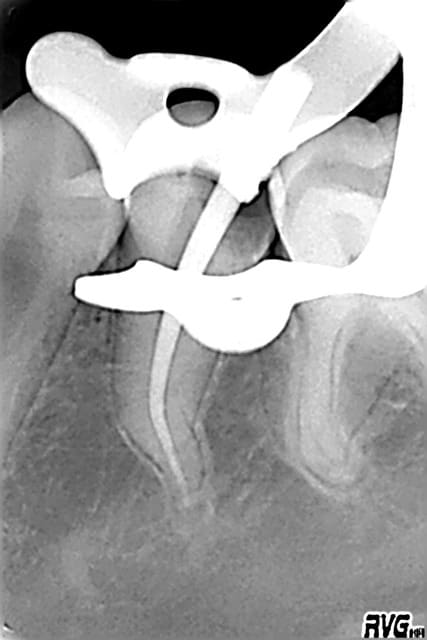

Pulpite sur 35 ce soir en urgence (je vous assure que j'ai pas de carie, je regarde tous les jours), la main qui tient la joue, la corne pulpaire ouverte qui rythme en rouge. Une bonne vingtaine de minutes pour l'endo grâce à l' anesthésie instantanée.